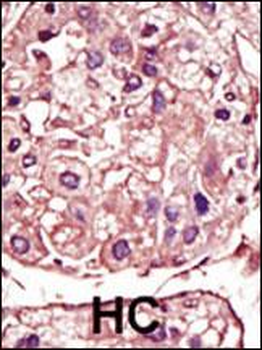

Anti-TGFBR1 / ALK5 antibody IHC staining of human small intestine. Immunohistochemistry of formalin-fixed, paraffin-embedded tissue after heat-induced antigen retrieval.